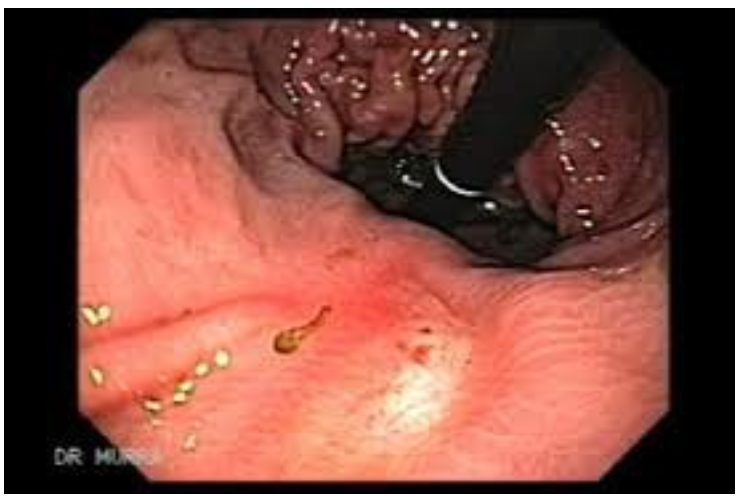

Dieulafoy lesion